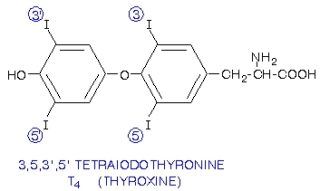

fenilalanin- tirozin amino asitleri: aminoasitler arasında özellikle tirozine karşı bi hayranlığım var. neredeyse her taşın altından(abartıyorum) çıkan bir aminoasit. öncelikle fenilalanin ve tirozinin moleküler yapısından bahsetmem gerekir. bu iki aminoasit halkasal bir radikal gruba sahiptir. bu grup benzen halkasının türevleri olan fenil ve fenol gruplarını taşır. ve hormonlar nörotransmitterler ve sitokinler arasında benzen fenol ve fenil halkası bulunduran tüm yapılar tirozin ve fenilalanin aminoasitlerinden sentez edilir.

bunları fotoğraf ile göstereyim:

şu gördüğünüz tiroid hormonu (t4). yanındaki 2 halkaya dikkat edin lütfen

evet... bu hormonların hepsi tiroksin aminoasitinden sentezlenir. çünkü tiroksin aminoasitinden bu halkasal yapı alınarak başka moleküller ile birleştirilip bu hormonlar oluşturulur. bu halkasal yapılar, benzen, fenil- fenol ve benzeri yapılar şeker, yağ gibi besinlerde bulunmaz. yalnız tirozin ve fenilalanin aminoasitinden elde edilebilir. dışarıdan almak zorundasınız, zira vücudumuzun bu molekülleri sentezleme yetenekleri yoktur-sınırlıdır. ve bu aminoasitler olmadan bu adı geçen hormonları sentezleyemezsiniz. bu da vücudunuzun genel işleyişini bozarak ciddi metabolik hastalıklara yol açacaktır.